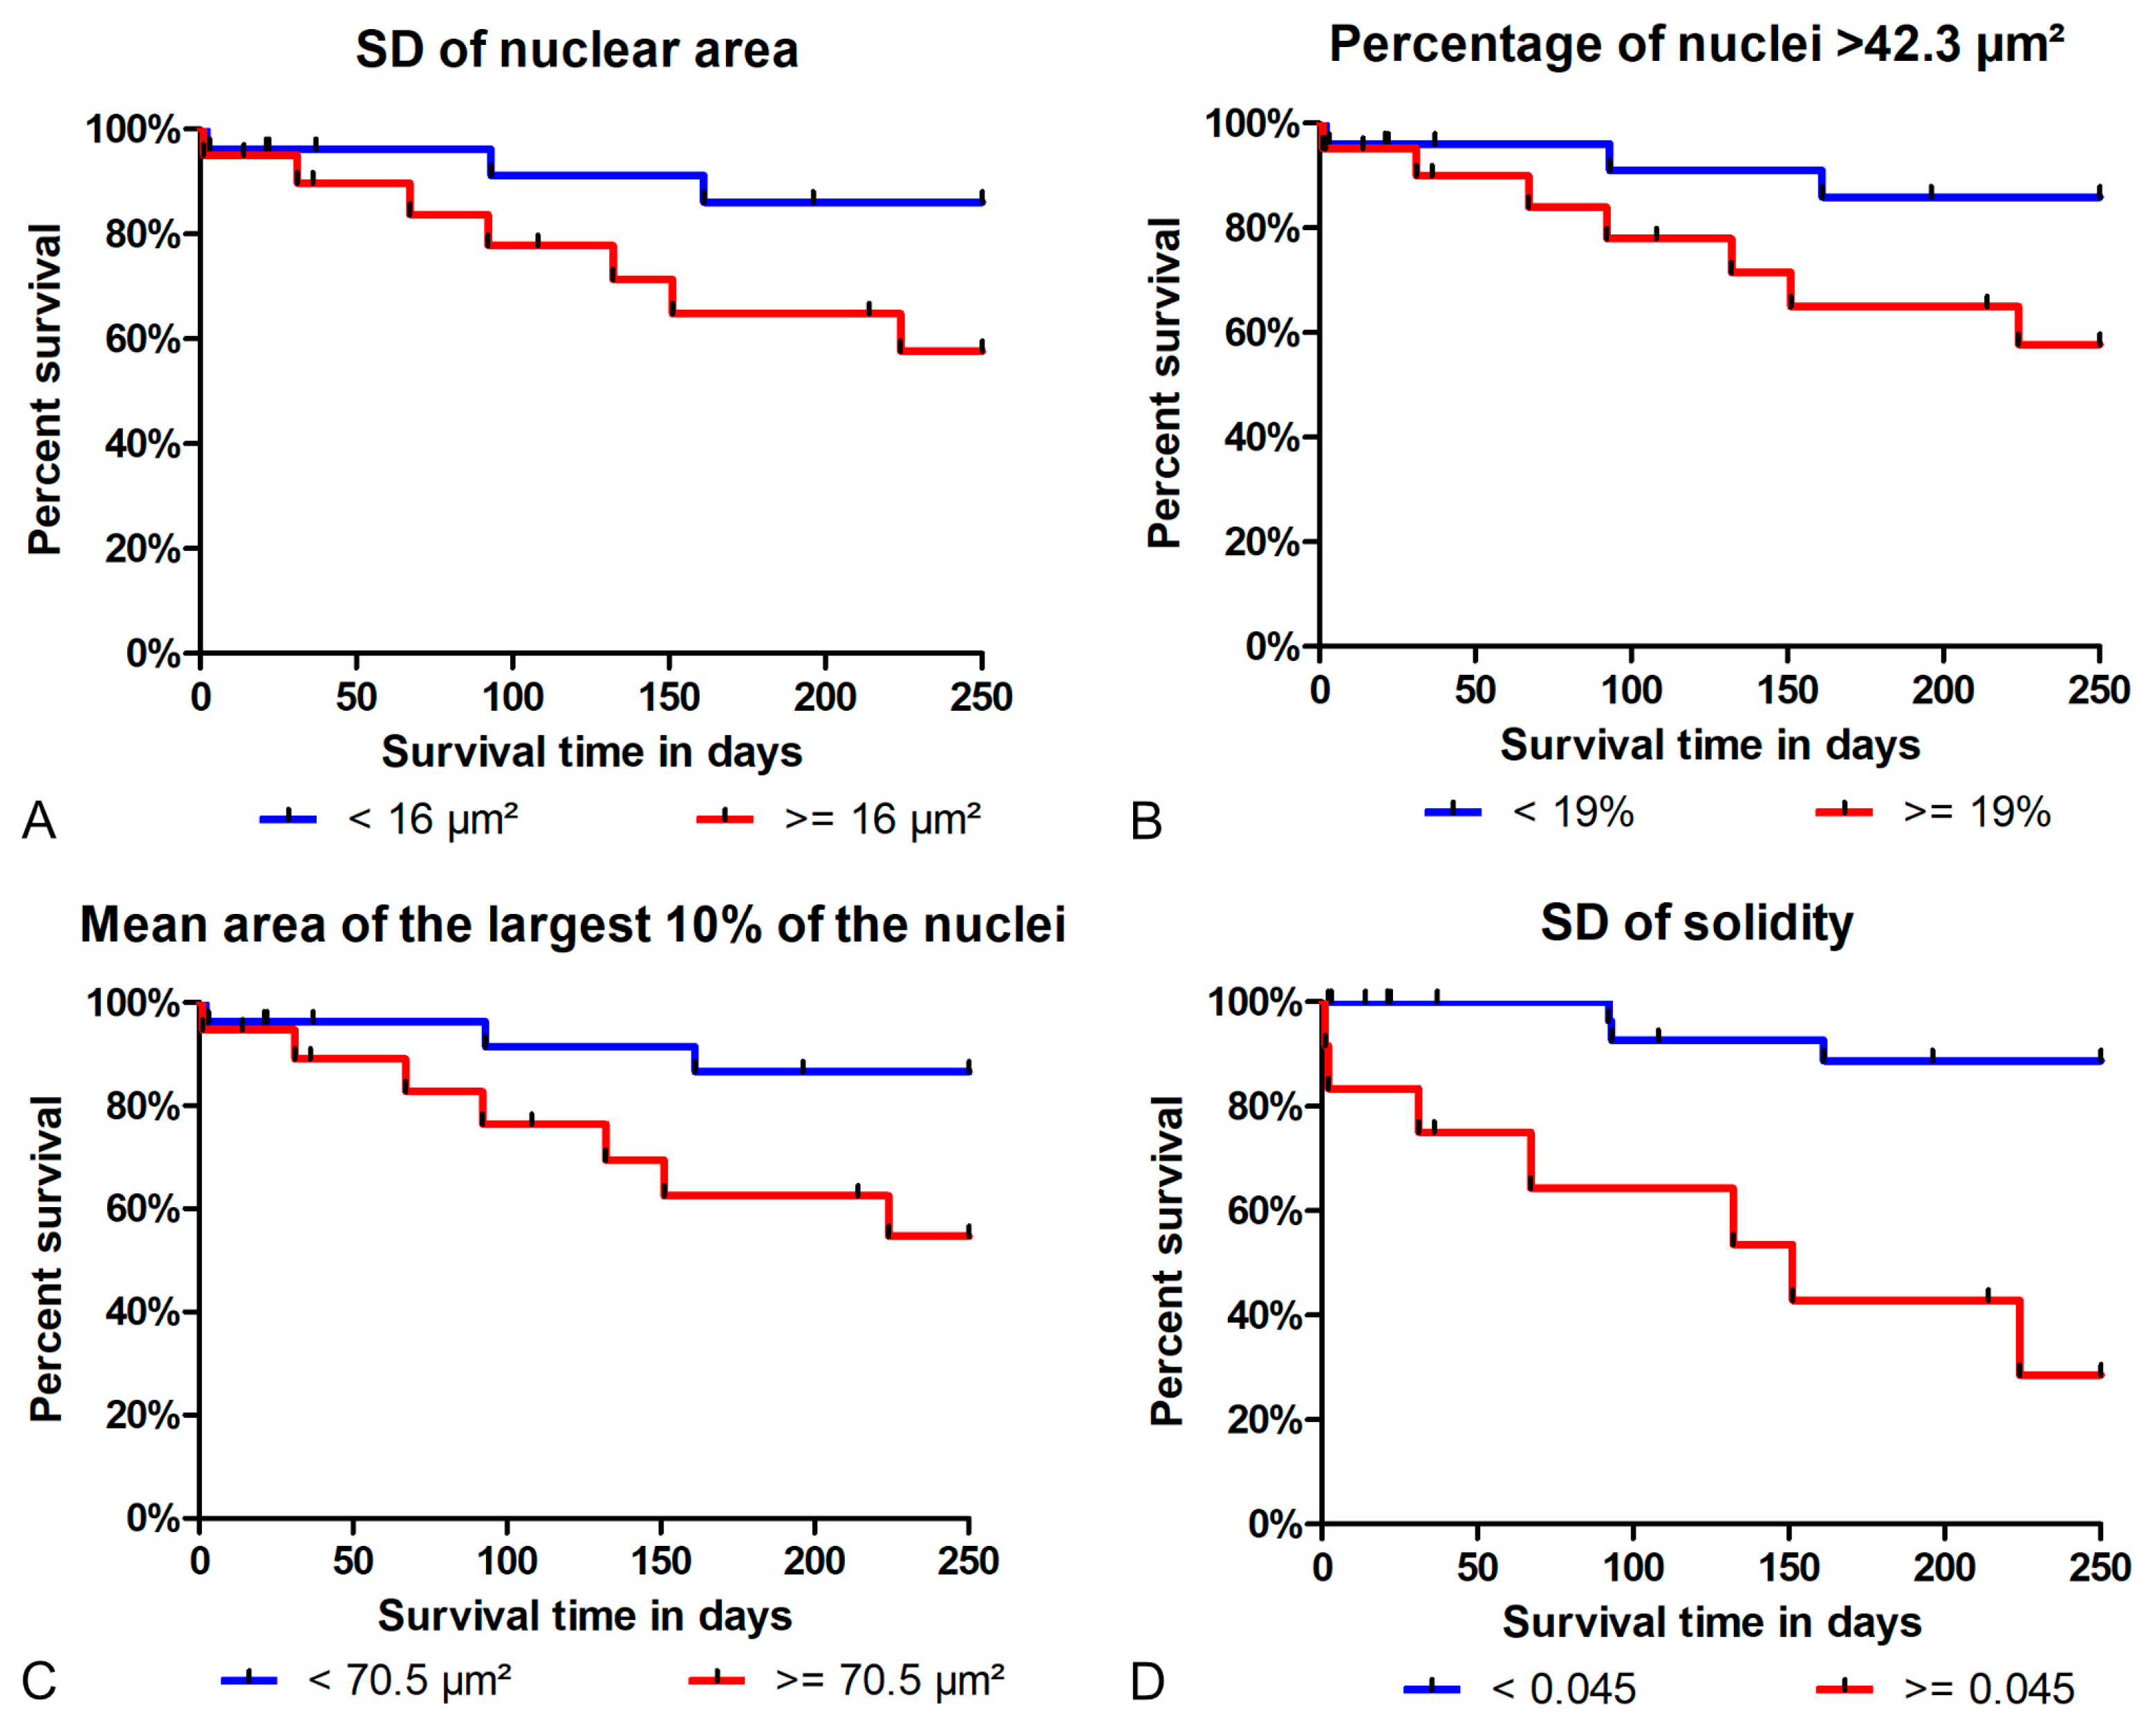

3.2. Test Accuracy of Algorithmic Morphometry

3.3. Prognostic Value

- Regarding tumor-specific survival, the prognostic ability of the algorithmic morphometry was similar to manual morphometry for most parameters, with the exception of SD of solidity, and other established prognostic tests (histological grade, mitotic count, and clinical staging). The algorithm has the advantage of efficiency as a large number of nuclei can be measured within a few seconds and thus makes morphometry feasible for routine diagnostic service.

| Prognostic Test | Algorithm | Pathologists | |||

|---|---|---|---|---|---|

| Threshold | HR (95%CI) | Threshold/Categories | HR (95%CI) | ||

| Morphometry | SD of area | 16 µm2 | 3.38 (0.87–13.1) | 10 µm2 | 3.32 (0.85–12.9) |

| Mean area of largest 10% of nuclei | 70.5 µm2 | 3.85 (0.99–15.0) | 50 µm2 | 9.83 (1.24–78.1) | |

| % nuclei above 42.3 µm2 | 19% | 3.32 (0.85–12.9) | 26% | 4.34 (1.12–16.9) | |

| SD of solidity | 0.045 | 9.88 (2.52–38.7) | 0.0204 | 1.94 (0.50–7.52) | |